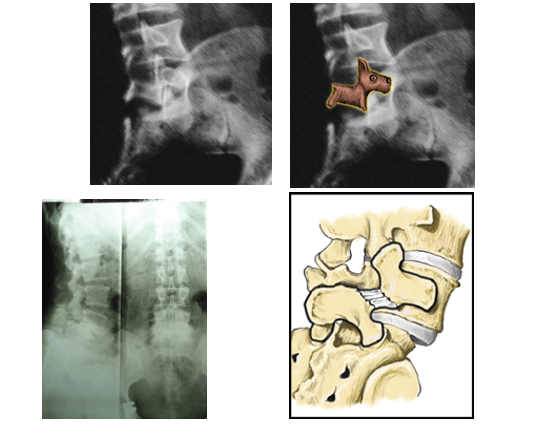

trượt đốt sống lưng

Trượt đốt sống lưng : Nguyên nhân, triệu chứng, chẩn đoán và điều trị

Chuẩn đoán trượt đốt sống lưng

Nguyên nhân gây trượt đốt sống

Chuẩn đoán mức độ trượt đốt sống